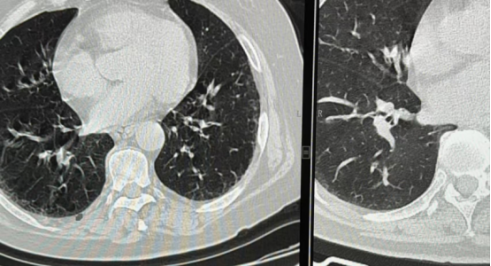

左图呼吸配合不佳,图像较右图模糊

✓ 肺叶如降落伞般完全展开,0.5mm以上病灶无所遁形

✓ 消除呼吸运动伪影,避免将膈肌波动误判为病变